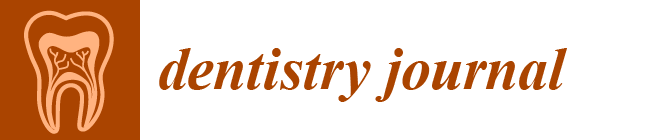

2.1. Study Design, Patient Treatment Characteristics

2.3. Modeling